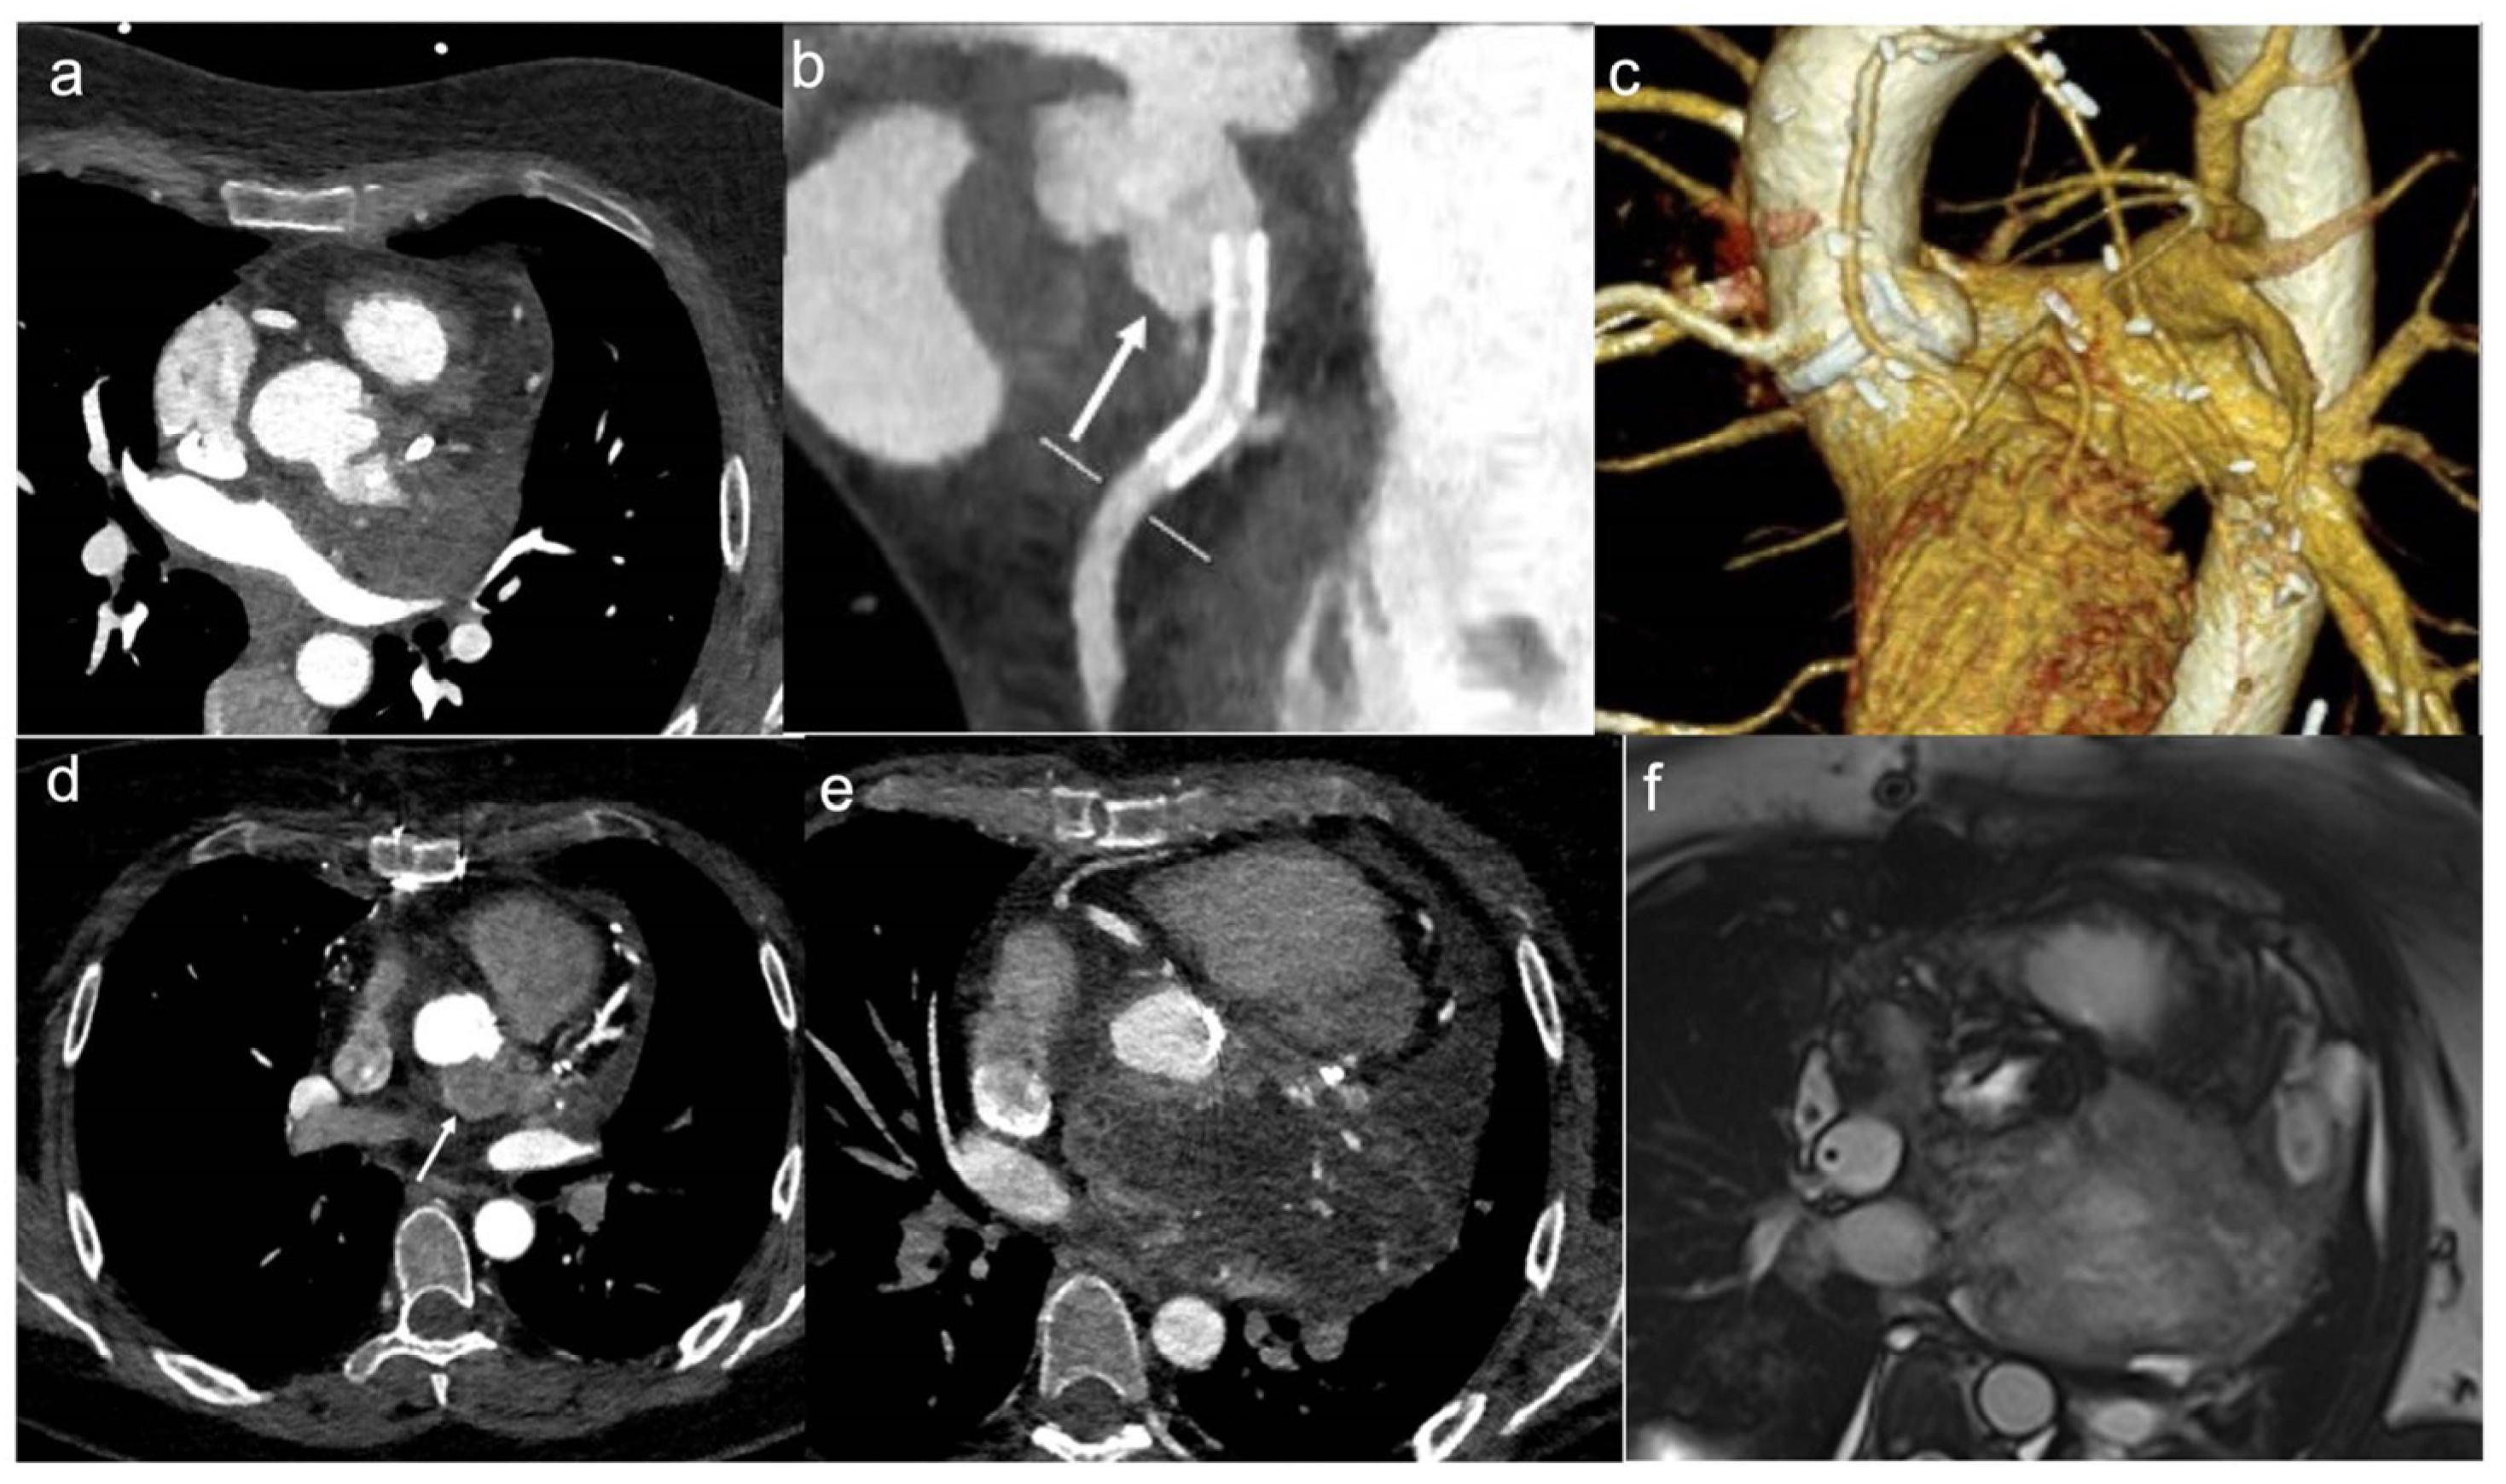

Figure 1.

A 46-year-old woman with retrosternal pain during exertion and non -ST elevation myocardial infarction underwent coronarography. The interventional procedure showed stenosis of the common trunk treated with bifurcation stent implantation. Later, due to the unexplained pericardial effusion, the patient underwent coronary computed tomography angiography (CCTA) which revealed a voluminous pseudoaneurysm (arrow) of the left coronary sinus (a,b). Cardiac surgery was performed to exclude pseudoaneurysm and to perform a by-pass (c). After the cardiac surgery, the patient performed a CCTA that showed the exclusion of the pesudoaneurysm (d). Four months later, when the patient was back for a follow-up, CT angiography showed a mass with peripheral enhancement, central hypodensity due to necrosis, and central neoangiogenesis (e). Finally, the patient underwent CMR that confirmed the presence of inhomogeneous mass invading the surrounding structures (f) and neoplasia was suspected. Lastly, the ultrasound-guided transesophageal biopsy has shown the presence of fused and pleomorphic malignant cells with leiomuscular immunophenotype (actin 1A4 +) and the diagnosis of leiomyosarcoma was made.